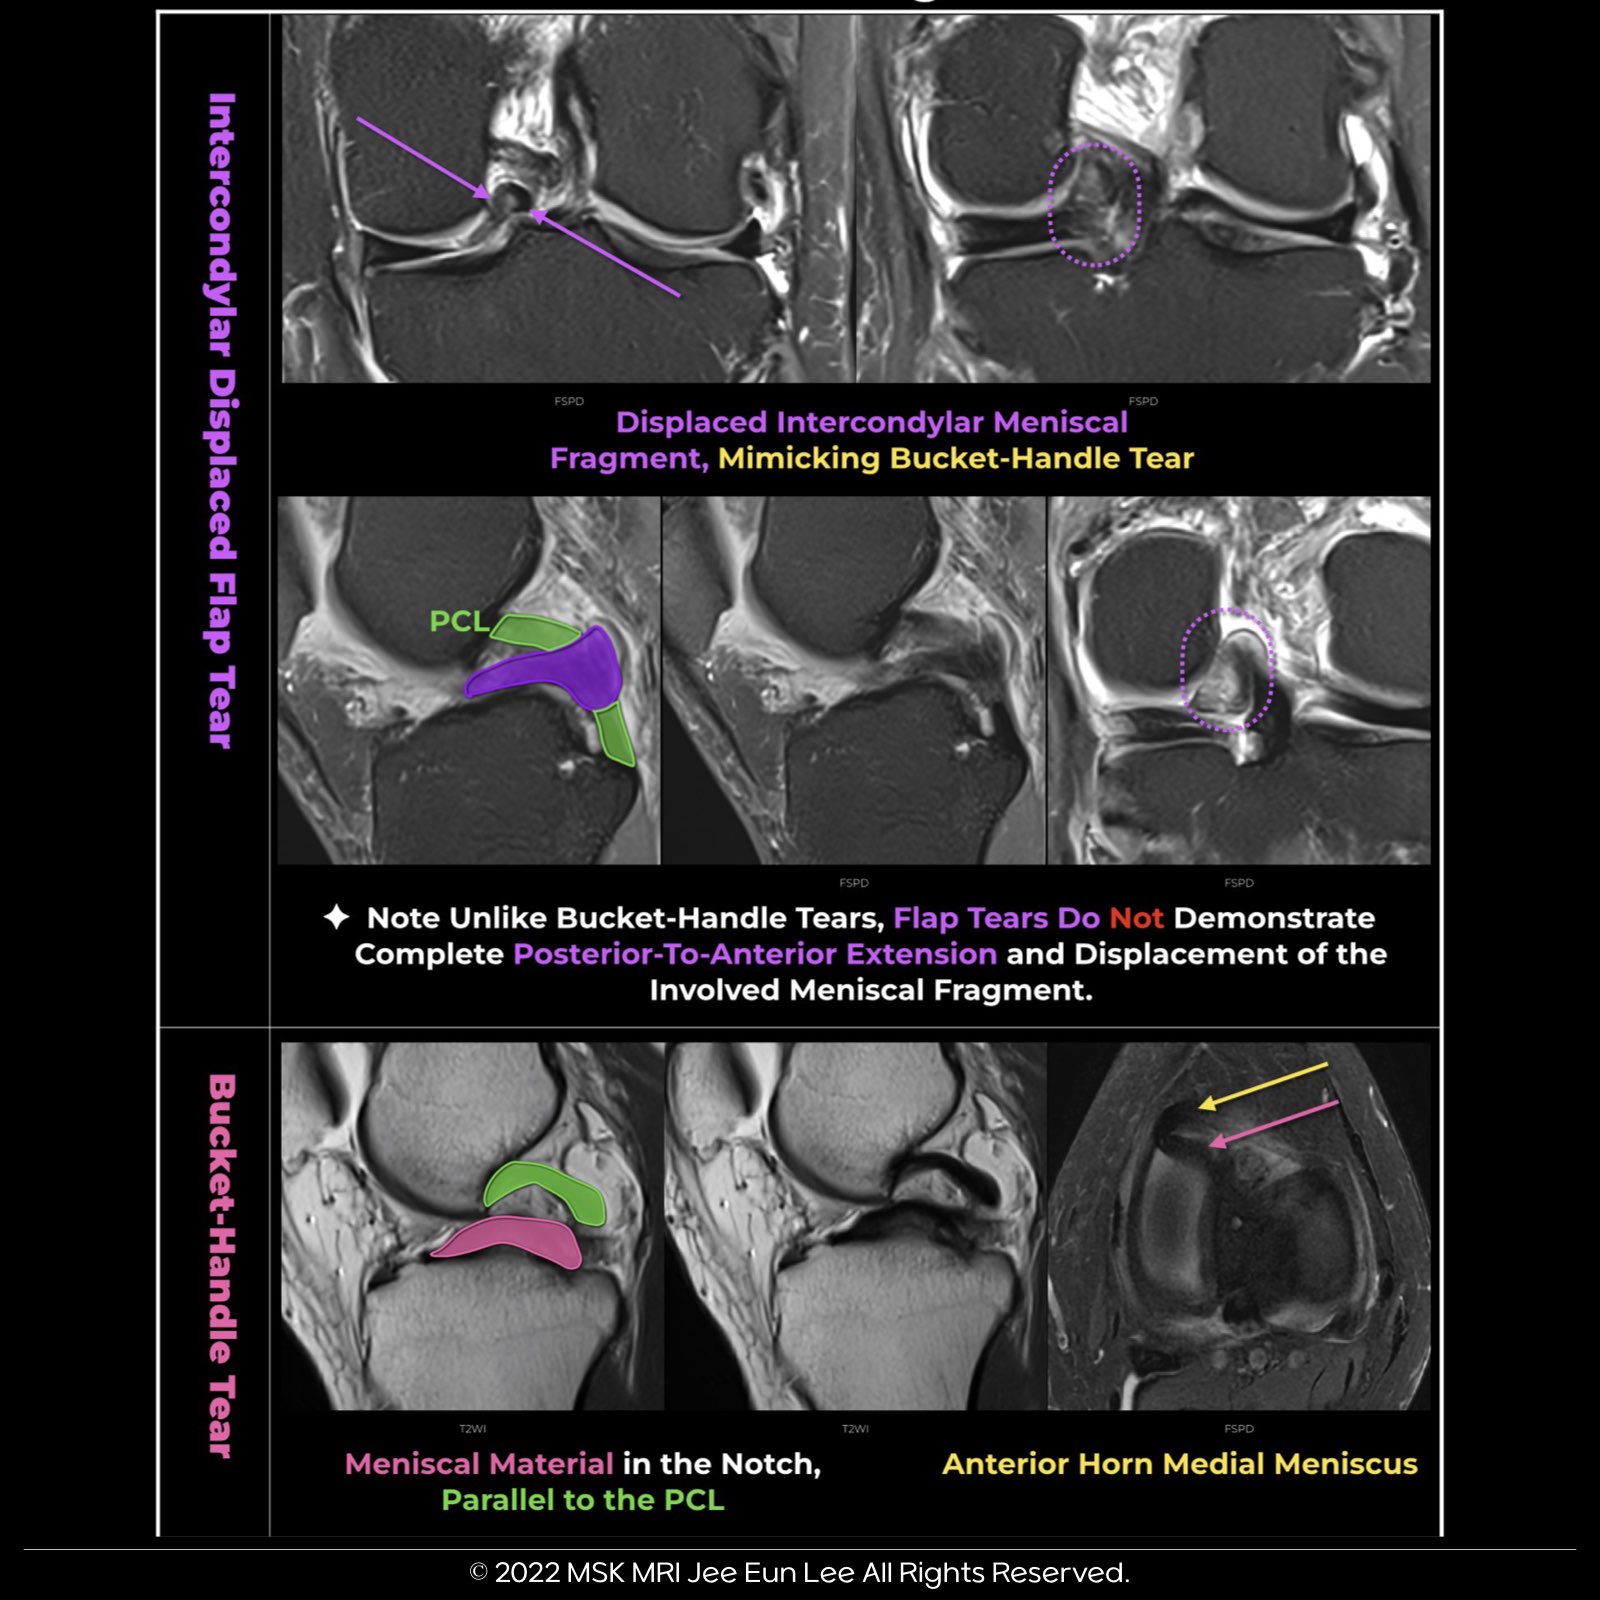

Flap Tear vs. Bucket-Handle Tear:

- Flap tears, unlike bucket-handle tears, do not show complete posterior-to-anterior extension and displacement of the involved meniscal fragment. In this scenario, the flap tear mimics a bucket-handle tear, yet distinct differences are evident upon closer examination.